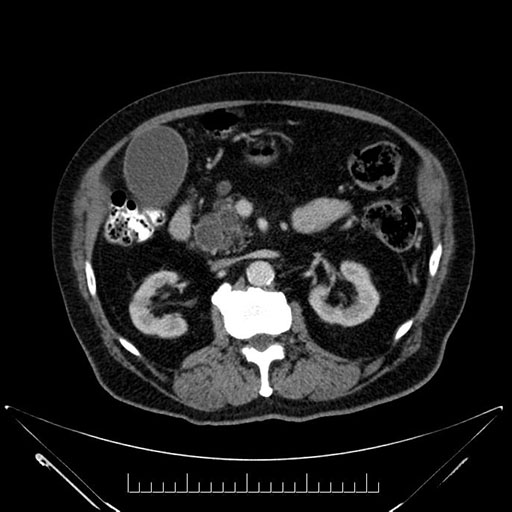

Imaging Analysis

Look through the patient's CT scan to identify any areas of concern for the necessary procedure.

Based on your CT findings, which issue(s) would give reason for "planned slowing down moment(s)" in this case?